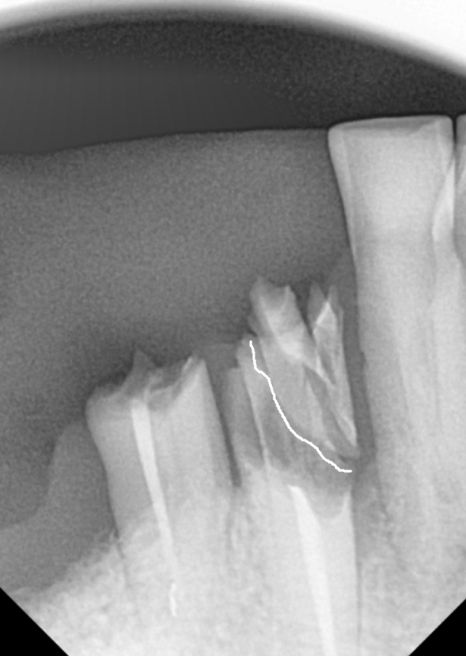

무엇보다 브릿지를 지탱하던

앞 치아(#43)는

과도한 힘을 버티지 못하고

치아 반쪽이 깨져 있었습니다.

250507

맨 끝 치아(#47) 역시 뿌리 끝에

고름주머니가 크게 잡혀 있었죠.